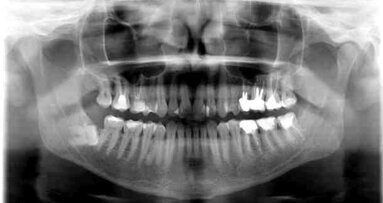

Dwudzielny kanał żuchwy jest anatomiczną odmianą budowy kanału żuchwy oznaczającą, że kanał żuchwy jest podzielony na dwie gałęzie. W ...